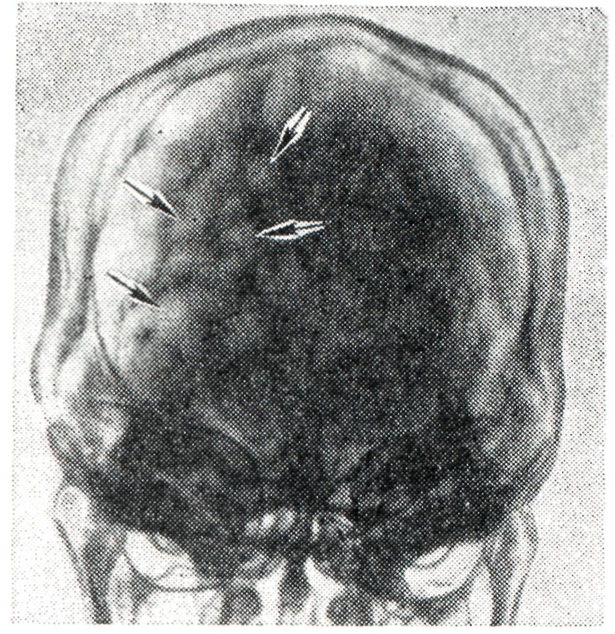

Иногда наблюдаются эпилептические припадки. Отмечены нарушения психики, в редких случаях — слабоумие. Могут быть патологические рефлексы, атаксия, эндокринно-обменные и вегетативные нарушения. Сочетание Б.ч. с прогнатизмом, экзофтальмом, нистагмом, умственной отсталостью, эпилептоидными приступами, атрофией зрительного нерва описывается как синдром Терсиля. Могут быть стационарные (компенсированные) и прогредиентные формы Б. ч. На краниограмме отмечается отсутствие черепных швов в сочетании с Б. ч., наличие выраженных пальцевых вдавлений (рис.), укорочение и западение передней и средней черепных ямок, булавовидная спинка турецкого седла.